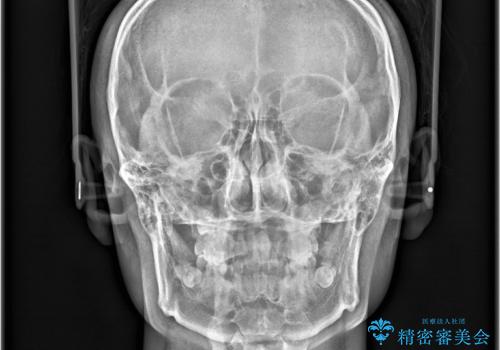

- 歯のデコボコと過蓋咬合を主訴に来院された患者様です。

アーチの拡大とIPRを行い非抜歯で治療を行いました。

歯を抜かずに叢生(デコボコ歯列)と過蓋咬合を改善する事が出来ました。